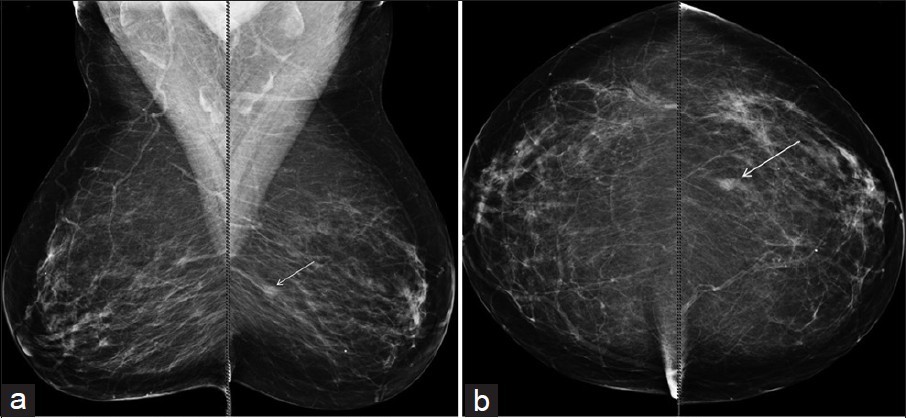

Mammography is the only imaging method that can show small foci of calcification, which is the earliest sign of breast cancer. When breast cancer grows and forms a mass or change in the breast skin in such a way that it is handled, it is noticed by the patient manually or by eye, it coincides with many years after the cancer has formed.

Tomosynthesis, often referred to as 3-dimensional mammography, uses low-dose X-rays to create 2D and 3D-like images of breasts. The patient experience is the same as that of a routine digital mammogram. But the computer creates thin slices of images of the breast. The radiologist can scroll through the images as if Deciphering the pages of a book. This improves the ability of mammography to find small breast cancers. It also reduces the number of patients called for Octograms, such as additional spot mammograms for non-cancerous conditions.